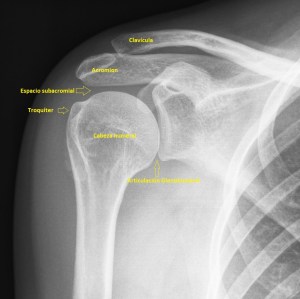

232. Impingement del Hombro

La exploración del protocolo de hombro debe incluir siempre las dinámicas de los diferentes tendones a estudio.

Hoy, en este breve post, te explico uno de los más importantes, que es la dinámica del Tendón del Supraespinoso para descartar el impingement por el cual se ve comprometido el normal paso del tendón del supra por debajo del espacio subacromial por una buena variedad de causas que te explica superbien aquí, es importante entender la anatomía, y también la mecánica lesional de la ecoestructura que testamos ecográficamente.

La anatomía radiológica que interviene es este estudio específico de la maniobra dinámica del tendón del supraespinoso te la dejo aquí.

1

Una vez que hayas visto el vídeo explicativo de youtube y revisado la anatomía radiológica de la imagen 1, quiero que aprendas a realizar la maniobra, imagen 2 y 3, con la que vamos a estudiar el tendón del supraespinoso a su paso por el espacio subacromial, que es, realizando una abducción del brazo partiendo desde la posición de reposo del húmero justo al costado y llevándolo mediante dicha abducción hasta los 90º del húmero con respecto al costado…mira:

Es importante tener localizado ecográficamente la articulación acromio clavicular (AAC) con la ecografía, posicionando el transductor, línea roja, como ves en esta imagen 4, donde debes cubrir toda la anatomía radiólogica explicada antes, mira:

4

Y lo que debes ver ecográficamente es esto: